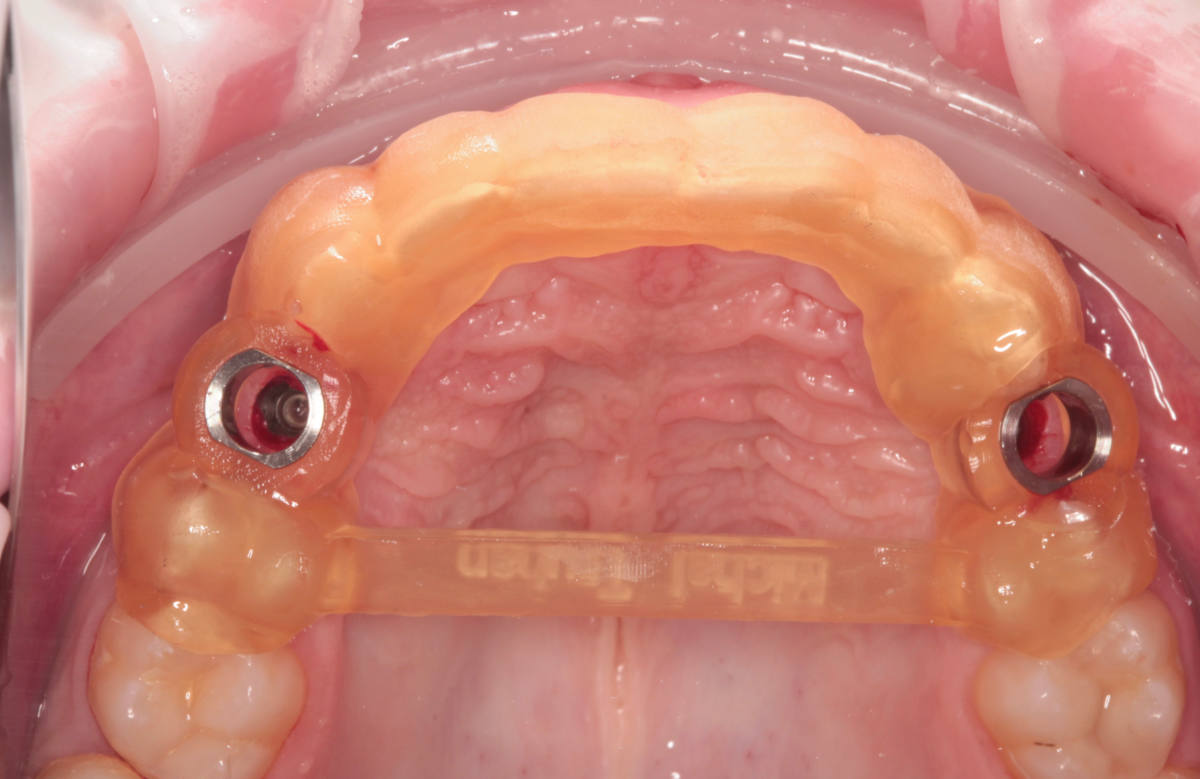

Navigovaná chirurgia, 3 implantátov

Autor práce Dr. Michal Repaši

Zubný technik Vasil Csopej